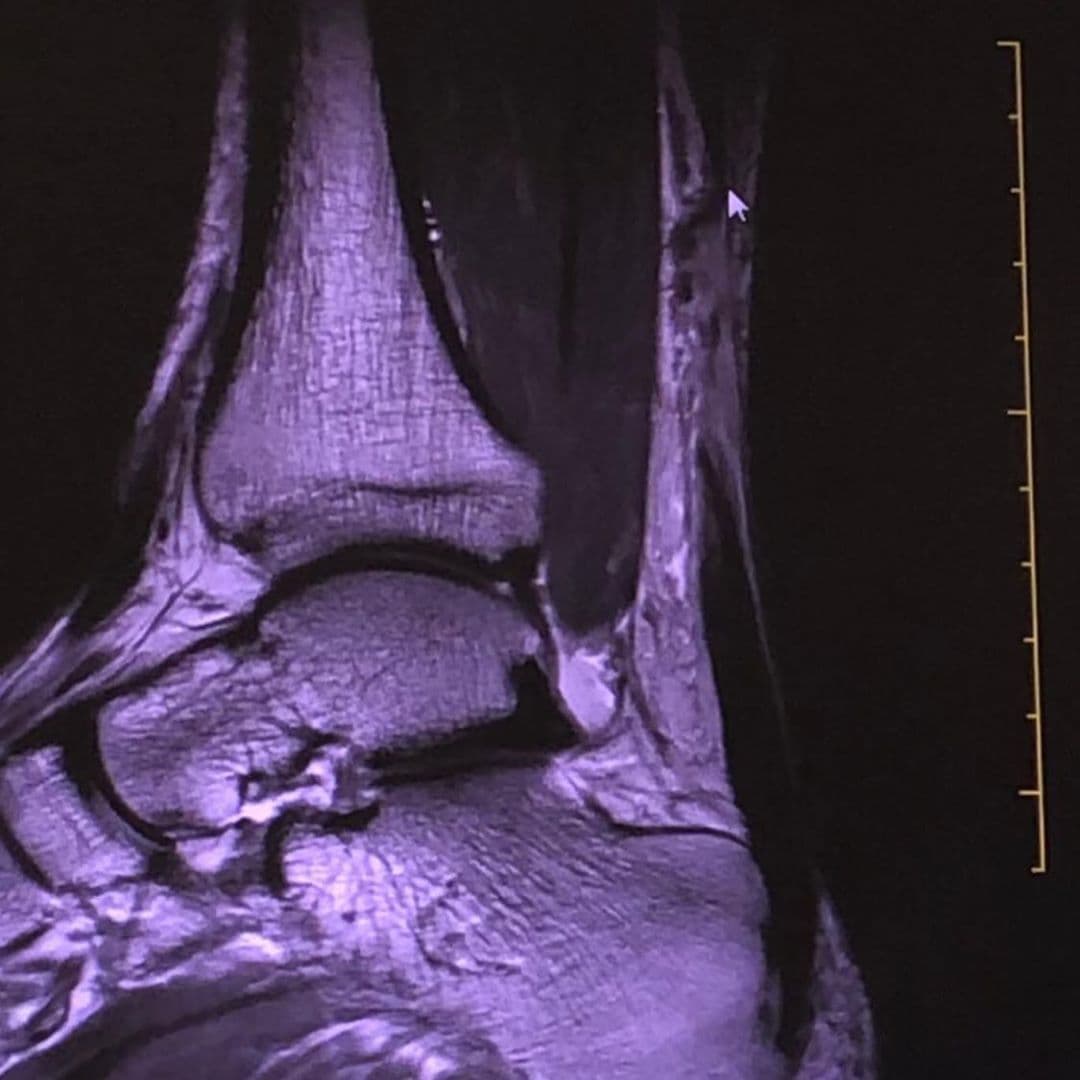

El lunes 8 de julio, el público de Despierta América obtuvo de primera mano el informe de salud de Carlos Calderon, ya que el Dr. Juan acudió al show para hablar del diagnóstico del presentador: roptura del tendón de Aquiles. Raúl González también entrevistó a Carlos, quien contó que se encontraba asustado por la operación que al poco tiempo se sometería.

Despierta América estuvo al pendiente de los procedimientos de Carlos Calderón. Luego de la cirugía conversó durante una transmisión sobre la intervención de emergencia que le practicaron para reparar el tendón y aseguró haber quedado sorprendido con el novedoso método al que lo sometieron y agradeció al Dr. Juan por todo su apoyo.

Durante el programa también compartió las imágenes del procedimiento, alegando cómicamente que "la gente siempre ha querido conocerme por adentro, entonces por ahí pueden verme por un hoyito".